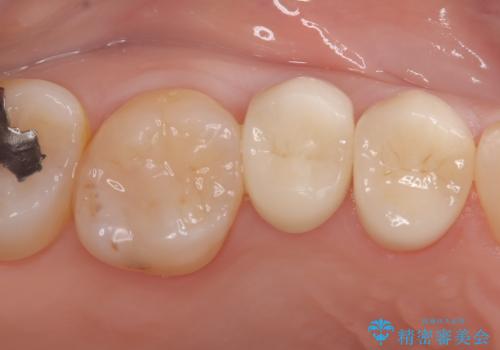

クラウンの装着時には適合状態を確認し、接着操作を丁寧に行いました。

治療後は審美性と機能性の両面で良好な状態が得られ、患者様にもご満足いただけました。